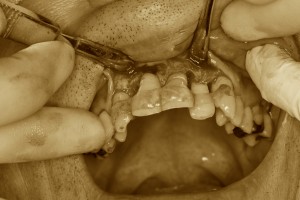

歯ぐきを開いてクリーニング

歯周病がひどく、SRPだけでは対処できないこともあります。

その場合は歯ぐきを開いて、歯ぐきの中が見える状態で徹底的にクリーニングを行います。

これを専門的にFOP(フラップオペレーション、歯肉剥離掻爬術)と言います。